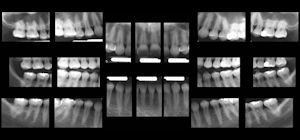

| The software also identifies regions of interest where 18 intraoral images would normally be taken, then extracts the images from a single panoramic x-ray to create an 18-image survey. |

He and his colleagues plan to publish a thesis on this that shows no significant difference between the panoramic bitewings and ordinary bitewings, he added. Such an advance could eliminate the need for intraoral bitewings, which can be uncomfortable, time-consuming, and overexpose the patient to radiation.

"A single digital pano image is five to 10 times less radiation than digital intraorals," Dr. Langlais said. "So, conservatively, the image of the pano system with tomosynthesis is five times less radiation than intraorals."